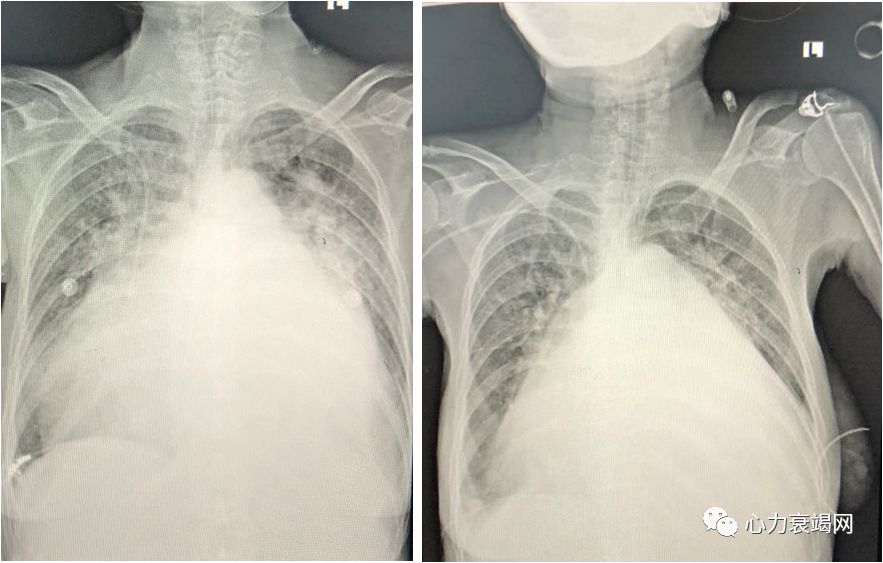

心影显著增大

肺淤血并炎症

纵膈增宽

全心增大: LA95mm LVEDd:66mm EF:53%

双侧胸腔积液(右侧已定位:94 × 70mm)